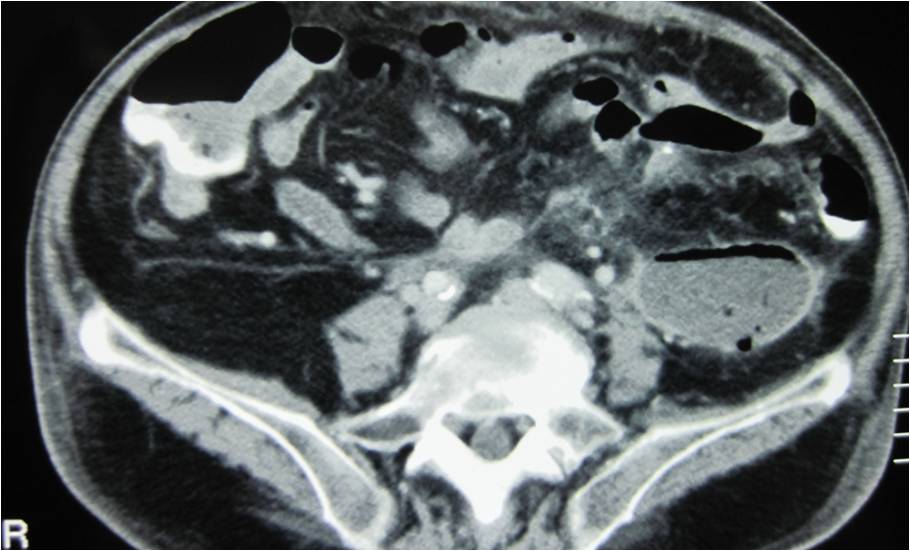

- Large abdominal abscess post- pancreatic surgery

- Successful drainage